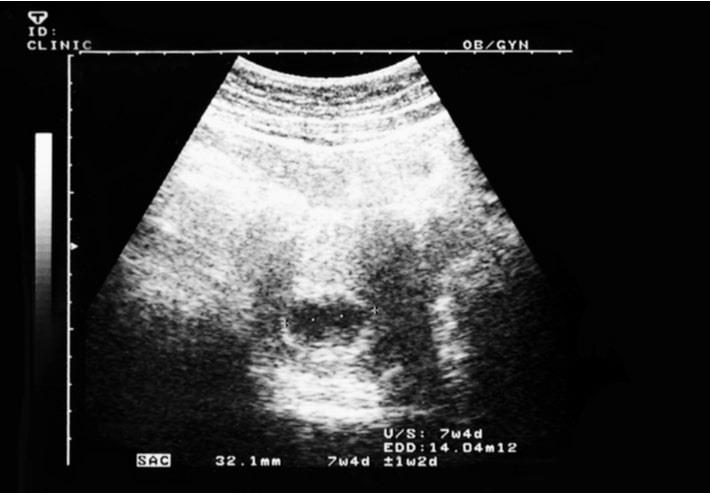

שבוע 7 להריון

אם עדיין לא עשית אולטרסאונד, השבוע תפגשי לראשונה את העובר שלך. מה תוכלי לראות באולטרסאונד ומה את צפויה להרגיש בשבוע זה? לפניך כתבה על השבוע ה-7 להריון

בדיקת אולטרסאונד ראשונה.